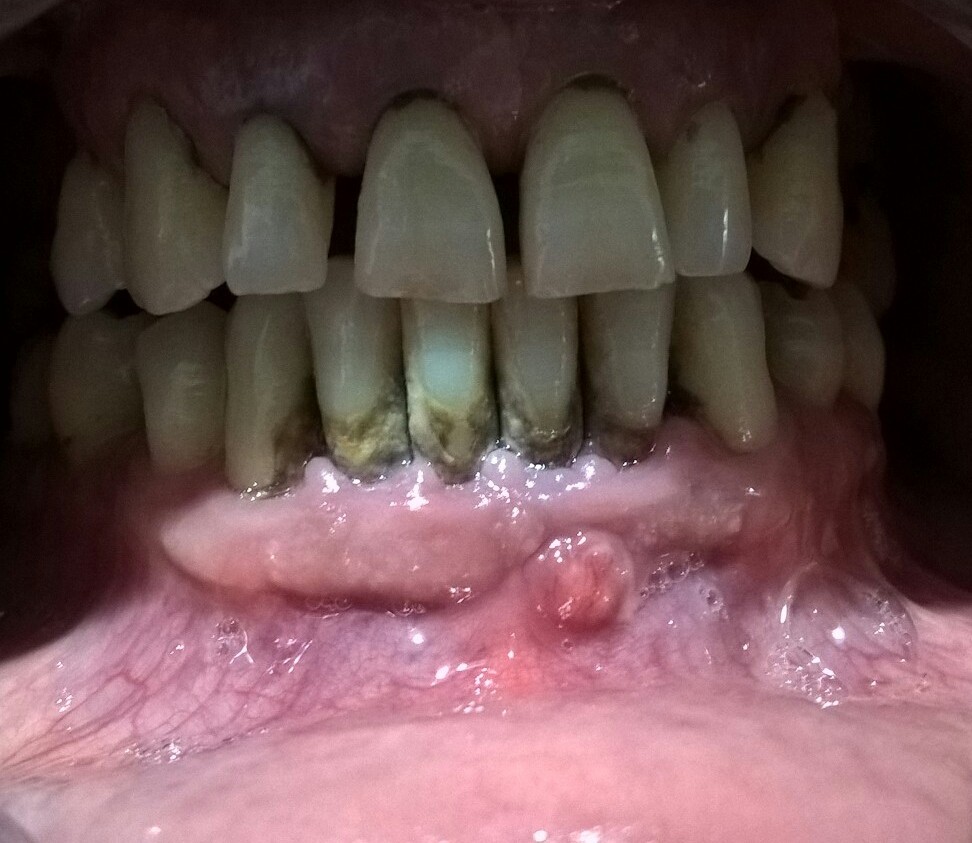

2.Imobilizarea dintilor mobili cu banda din fibra de sticla.

3.Tratamentul antimicrobian cu pasta TM.

4.Tratament antiinflamator, antiedematos si biostimulator cu laserul terapeutic.

Dupa cele 6 sedinte de tratament cu laser s-a efectuat indeparatrea tartrului subgingival cu chiurete Gracey.